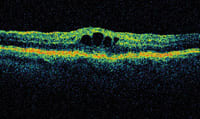

A line scan showing cystoid spaces in the retina consistent with

CME. |

A 67 y/o woman had cataract surgery 6 months prior with vitreous loss during the procedure. The patient had a history of dry macular degeneration with high-risk drusen. The best-corrected visual acuity was 20/25. Acuity recently dropped to 20/40, and the patient was referred for a retinal examination to rule out CNV. The OCT showed cystoid spaces in the retina, and no subretinal fluid was noted indicating cystoid macular edema, which was confirmed by the FA. Patient was treated with a topical nonsteroidal antiinflammatory drug (NSAID).